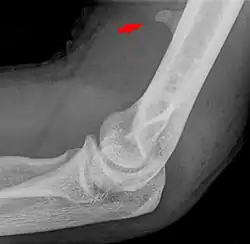

Processus supracondylaris im seitlichen Röntgenbild des Ellenbogens.

Der Processus supracondylaris ist eine seltene atavistische Bildung an der vorderen ulnaren Seite des distalen Endes des Oberarmknochens (Humerus), etwa 6 bis 7 cm proximal des Gelenkspaltes. Synonyme sind Processus supracondylicus, Tuberculum supratrochleare, Humerussporn und englisch Humeral supracondylar spur. Es handelt sich um einen knöchernen Fortsatz, der bei 0,7 % – 2 % aller Menschen vorkommt.[1] Die Erstbeschreibung geht auf den Anatomen F. Tiedemann im Jahre 1822 zurück.[2] (zitiert nach[3])